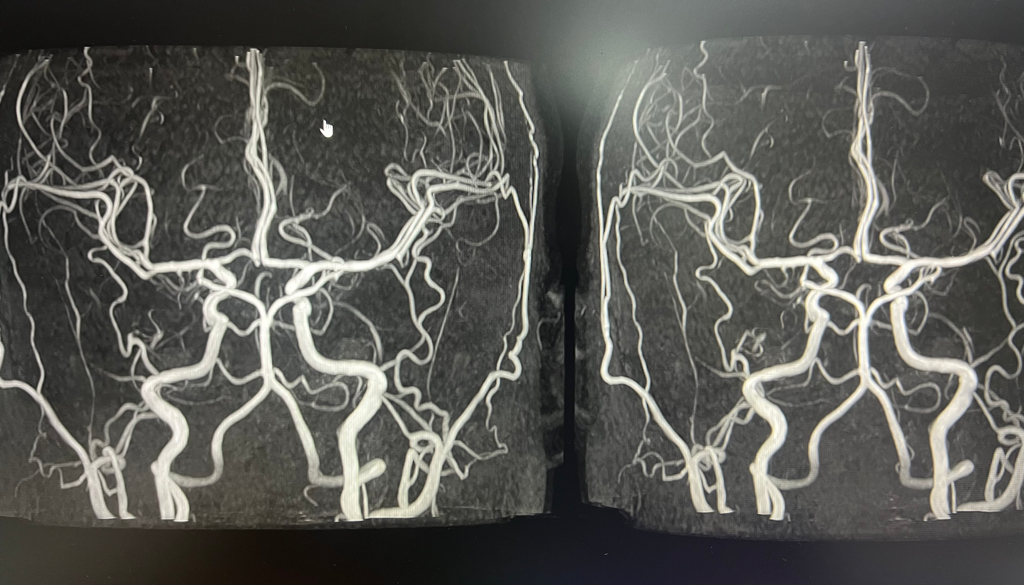

MRA 사진이네요. 사진만으로는 제한이 있지만 대동맥고리에는 이상은 없어 보입니다.

대동맥고리란 뇌에 분포하는 안쪽목동맥과 척추동맥의 가지들이 다각형으로 연결되어 고리를 이룬 것으로, 대뇌동맥륜, 대뇌동맥환, 윌리스고리 (Circle of Willis) 라고도 하며 전뇌와 후뇌의 혈액 공급을 제공하여 내부 경동맥과 척추뇌바닥 시스템 사이의 중요한 전달을 합니다.

한, 두 장면으로 MRA가 정상인지 아닌지 평가할수는 없지만 보여지는 혈관은 건강해보입니다.